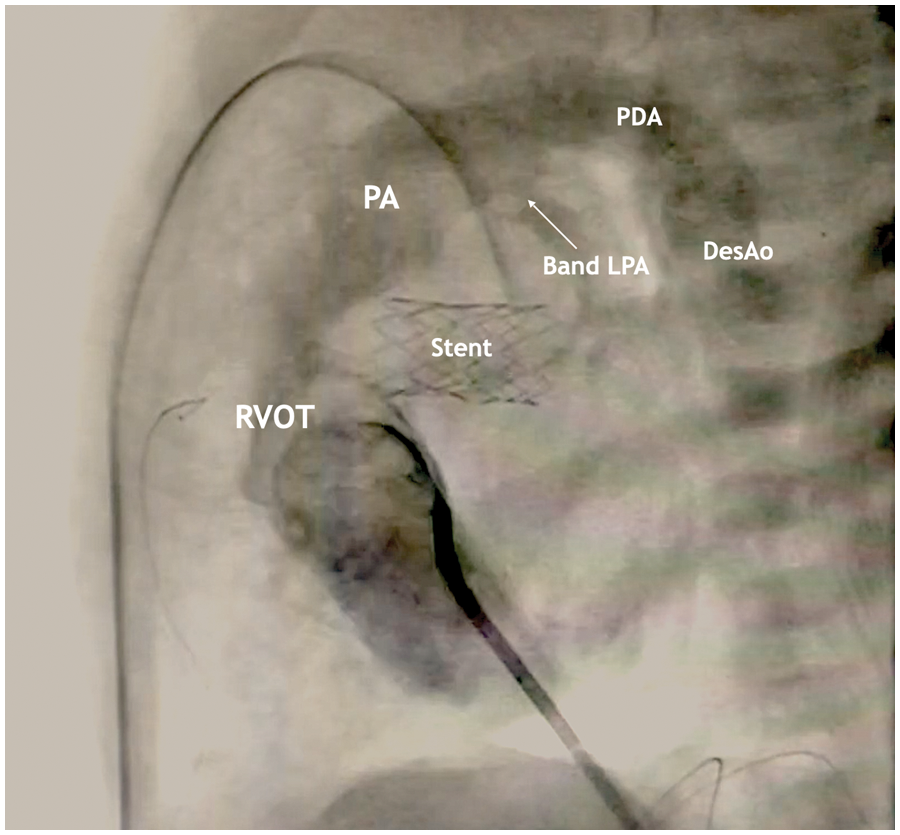

Figure 5: Lateral projection during cardiac catheterization with contrast

The stent is visualized in the projection of the atrial septal defect, the area of narrowing of the LPA, PDA with a diameter of 4 mm with a right-left shunt.

The first stage was planned to perform percutaneous balloon atrioseptostomy. Performed angiography of the chambers of the heart, as a result of which the flow at the level of the interatrial septum was not determined. Many attempts to perform atrioseptostomy were ineffective. A decision was made to perform an open atrioseptostomy through a median sternotomy. After performing the access, a purse-string suture was formed on the auricle of the right atrium with polypropylene monofilament thread 5/0. After that, a puncture of the atrial septum was performed, a 6 Fr introducer was installed, a balloon artrioseptostomy was successfully performed, and stenting of the atrial communication with a stent with a diameter of 6 mm was performed (Figs. 4 and 5).